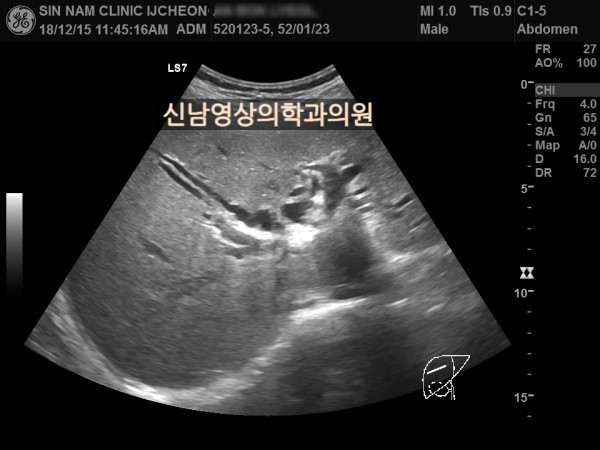

상복부 초음파 적용 사례

본 환자분은 50대 중반의 남성분으로 손가락안이 가렵다는 느낌으로 내원하셨습니다.

환자분은 황달 증세는 없었습니다.

빌리루빈 수치가 높아지면 소양증(가려움증)이 나타납니다.

피부의 밖이 아니라 속에서 느껴지는 가려움증으로 긁어도 해결되지 않는 것으로 복부 초음파 검사를 시행했고, 간내 담관들이 늘어나 있으면서 담도 하부에 혹이 발견되었으며, 이 혹은 담관밖으로 까지 퍼져있는 담도암으로 진단되었습니다.

간내 담관들이 확장되어 있을때는 담관을 막는 혹의 위치를 찾는 것이 중요하고, 이는 초음파 검사를 시행하는 의사의 숙련도가 갖춰져야 가능합니다.